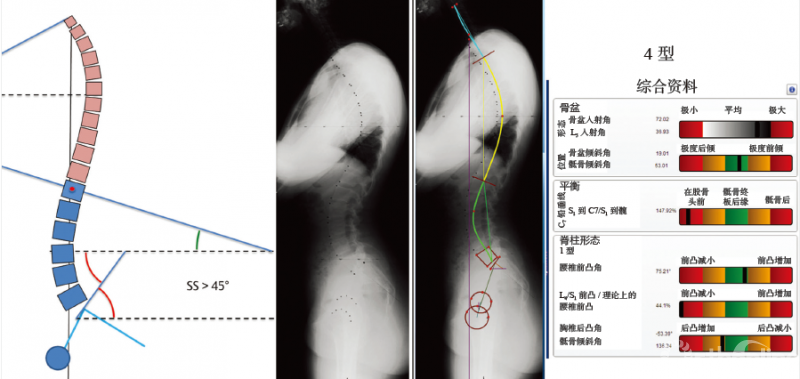

图 6-13 4型脊柱前凸

骶骨倾斜角>45°,前凸侧的椎体数目大于5个节段,存在节段性过度伸展状态